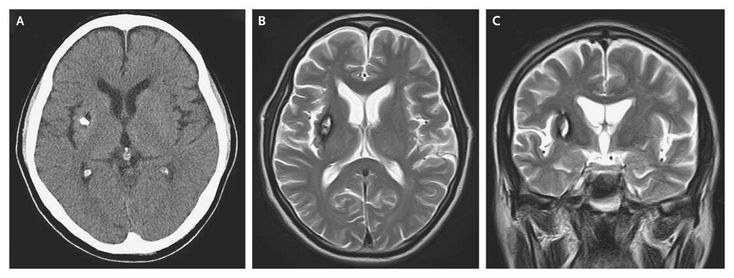

A 65-year-old man presented with a 10-year history of involuntary movements of his left hand. Neurologic examinations showed hemichorea in his left arm (see video) that disappeared during sleep. Computed tomography of the brain revealed a calcified lesion in the right putamen (Panel A). T2-weighted magnetic resonance imaging of the brain showed mixed signal intensity, with a central core and a peripheral rim of decreased intensity in the right putamen (Panels B and C) that suggested cavernous angioma. The results of magnetic resonance angiography were normal. Oral intake of haloperidol, sodium valproate, and zonisamide did not improve the symptom. Hemichorea is an occasional complication of various vascular disorders affecting the contralateral basal ganglia, but this manifestation is usually transient. Putaminal cavernous angioma, a rare cause of hemichorea, can yield an intractable pathologic circuitry among the basal ganglia and cortical motor areas.